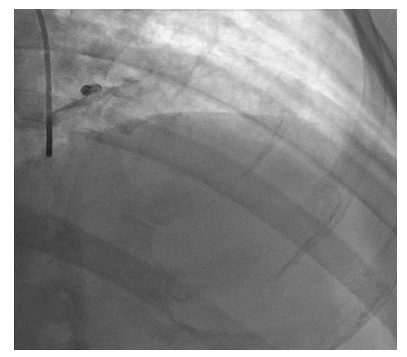

前:前降支主支血管阻塞